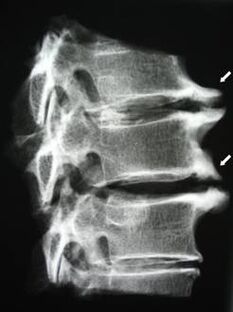

Nas fases iniciais, a osteocondrose detéctase mediante resonancia magnética. Máis tarde, a patoloxía pódese diagnosticar mediante radiografía. Nas radiografías da columna cervical, a diminución da distancia entre as vértebras, os cambios patolóxicos nas articulacións facetarias e a osteofitose fanse perceptibles.

| Osteocondrose cervical | A aparición de cambios patolóxicos nun ou máis segmentos de movemento da columna vertebral. Mobilidade da columna vertebral deteriorada, desenvolvemento de síndromes de dor miofascial e beliscar as raíces da columna vertebral | Dor, parestesia e alteracións motoras na rexión cervical, que se estenden á parte posterior da cabeza e aos membros superiores. Detección de cambios característicos na columna vertebral en resonancia magnética e radiografías (osteofitos, diminución da distancia entre as vértebras, signos de dano nas articulacións intervertebrais) |